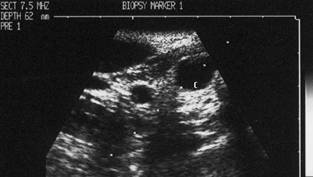

Barbat de 26 ani. Lobul drept al tiroidei: nodul chistic, anecogen cu intarire posterioara. Punctia se face in diagonala, acul traverseaza chistul spre de la suprafata spre baza si de la dreapta spre stg.

Imaginea dupa insertia acului. Varful acului este in centrul leziunii. Examen citologic: leziune benigna.